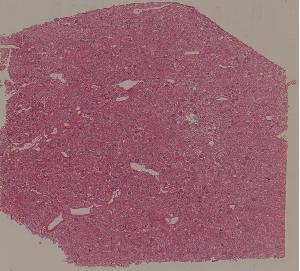

72. Lupus nephritis